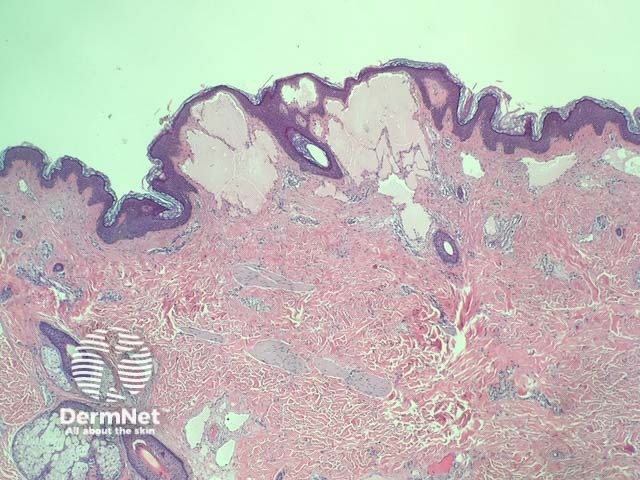

In lymphangioma circumscriptum, histopathological examination reveals acanthosis and hyperkeratosis of epidermis (figure 1). Within the papillary and reticular dermis, there are dilated lymphatic channels containing eosinophilic proteinaceous material in the papillary dermis (figures 2,3).

Figure 1